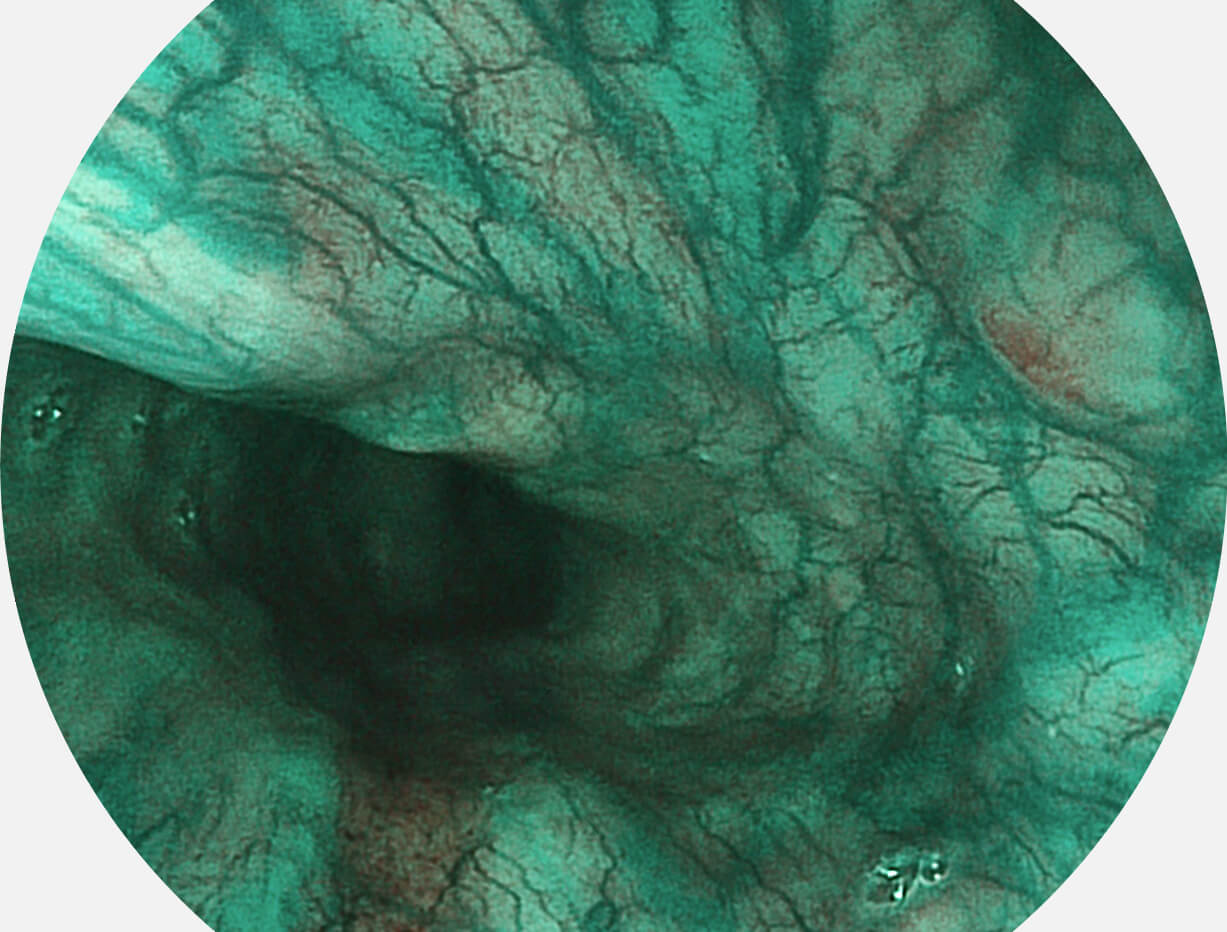

白光图像

VIST图像

Versatile Intelligent Staining Technology, VIST

强调浅层黏膜结构的同时,保证照明亮度和提升浅层微血管与中层血管颜色对比度,病变边界更清晰。